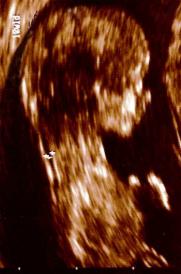

Der Kleine im Bild links könnte sagen: "Meine Nackentransparenz ist in Ordnung. Und ich habe ein Nasenbein und fünf Finger an der Hand. Und du?" Seine Nackentransparenz beträgt 1.3 mm und ist damit im Normbereich.